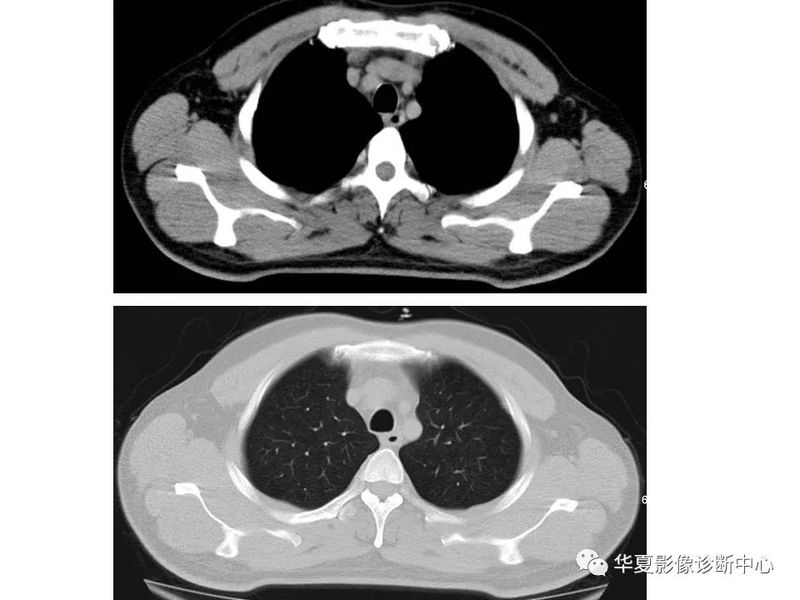

干货 | 汇总胸部CT读片扫盲知识,看懂胸部CT不再难